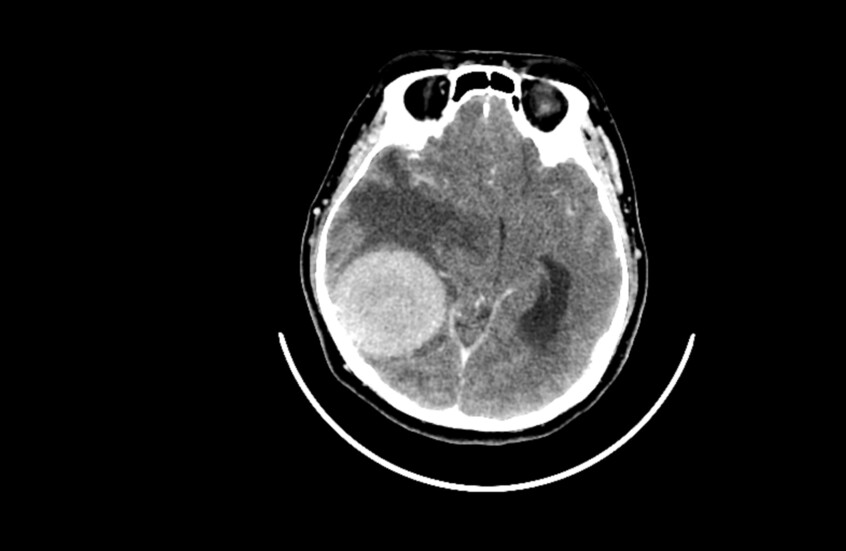

أعراض يومية شائعة قد تكون مؤشرات على أورام الدماغ

حذرت باحثتان من جامعة كوين ماري في لندن من أعراض يومية شائعة غالبا ما تُهمل “قد تكون في بعض الحالات علامات مبكرة على ورم في الدماغ”.

أكدت الباحثتان أن الكشف المبكر عن أورام الدماغ أمر بالغ الأهمية لتحسين فرص النجاة، حيث لا يعيش سوى ربع المصابين بأورام الدماغ في مراحلها المتأخرة أكثر من عام.